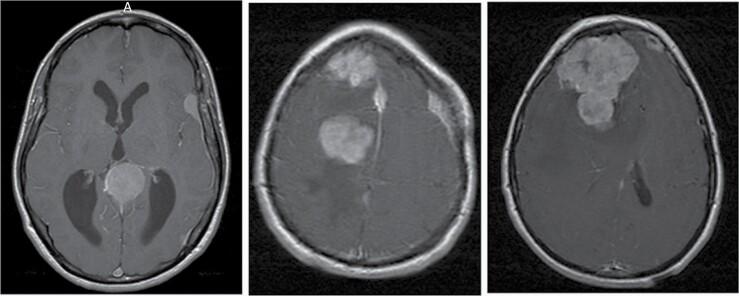

多发性脑膜瘤:流行病学、治疗及预后

Multiple meningiomas: Epidemiology, management, and outcomes.

脑膜瘤是成人中最常见的非恶性脑肿瘤,随着神经影像学的普及,无症状脑膜瘤的诊断发病率不断上升。一部分脑膜瘤患者患有2个或更多在空间上分离的同步或异时性肿瘤,称为“多发性脑膜瘤”(MM),据报道仅发生在1%-10%的患者中,尽管最近的数据表明发病率更高。MM构成一种独特的临床实体,具有包括散发性、家族性和辐射诱导性在内的独特病因,并带来特殊的管理挑战。虽然MM的病理生理学尚未确立,但理论包括通过独特的基因事件在不同位置独立起源,以及转化的肿瘤克隆通过蛛网膜下腔播散形成众多不同脑膜瘤的“单克隆假说”。尽管孤立性脑膜瘤通常是良性且可通过手术治愈的肿瘤,但患者仍有长期神经功能障碍和死亡的风险,以及健康相关生活质量受损的风险。对于MM患者,情况甚至更不利。MM应被视为一种慢性疾病,在许多情况下,管理目标是控制疾病,因为很少能治愈。有时需要多种干预措施和终身监测。我们旨在回顾MM的文献并创建一个全面的概述,包括基于证据的管理模式。